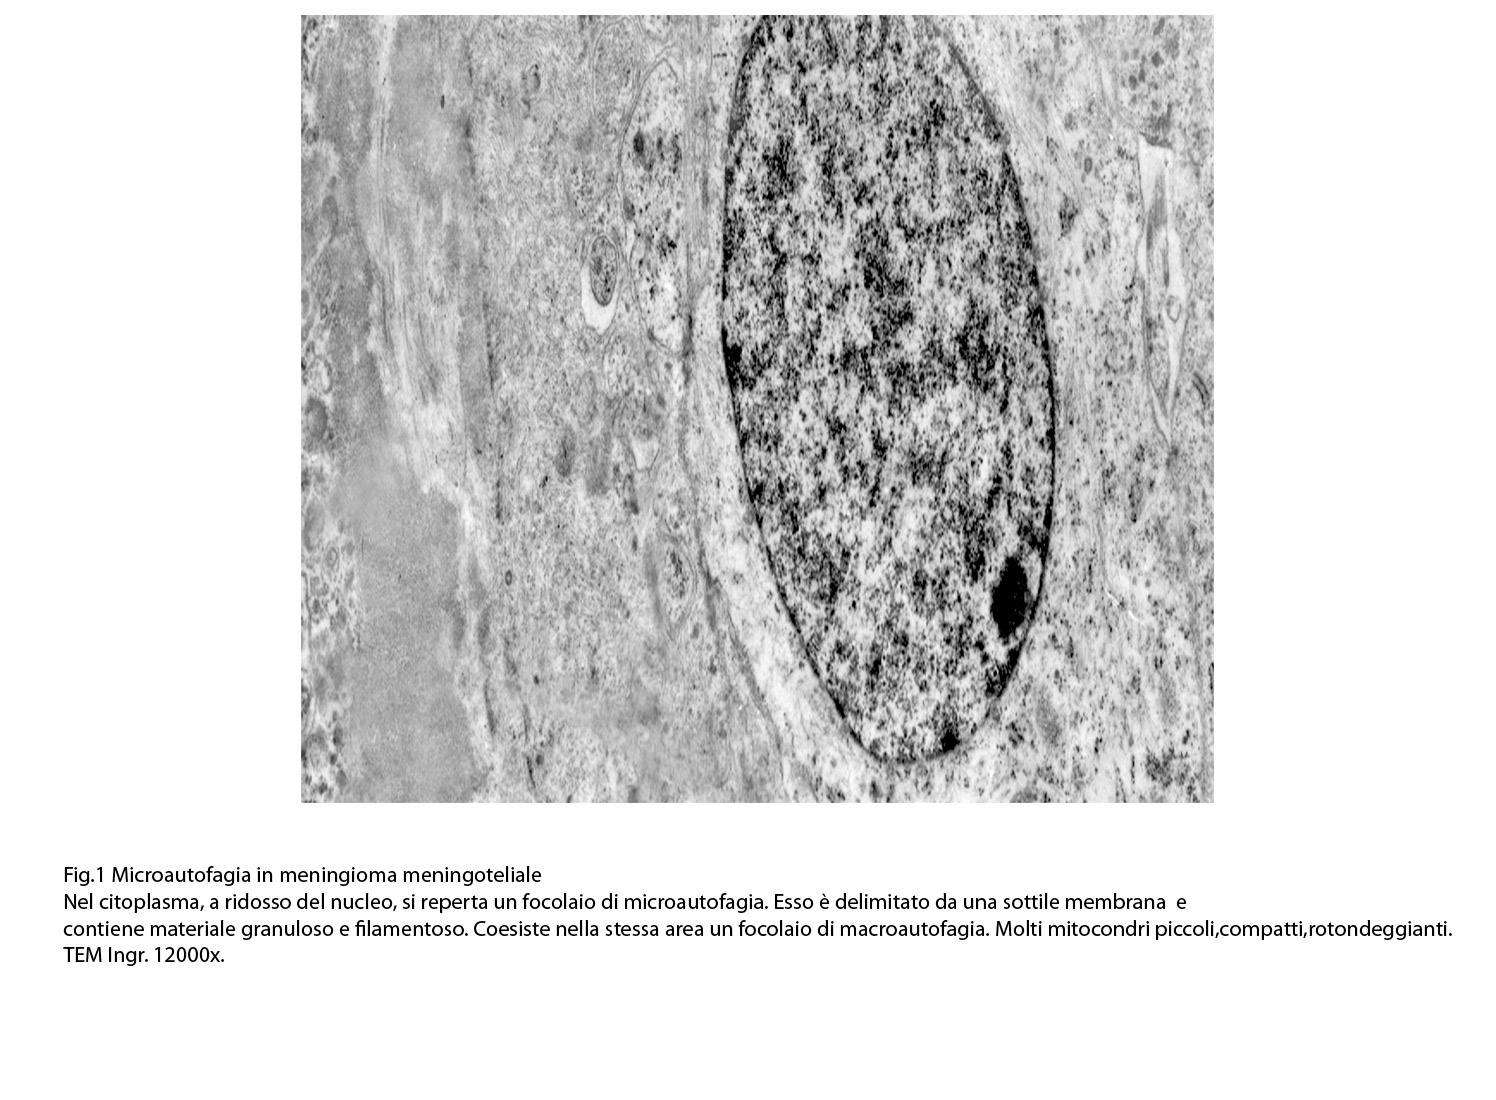

Al microscopio elettronico il citoplasma dei meningiomi meningoteliali appare ampio, ha un profilo irregolare, è fornito di prolungamenti citoplasmatici di varia lunghezza, ed è coeso alle cellule circostanti. Esso appare quasi sempre compatto anche se esibisce una densità del citosol molto variabile, fino ad immagini iperchiare, quasi trasparenti. E’ costantemente fornito di quote cospicue di organuli e di complessi proteici, e tutte queste substrutture sono distribuite in modo apparentemente uniforme nel citosol. Si evidenziano,infatti, numerosi quanto brevi segmenti di ergastoplasma rugoso, mitocondri piccoli, rotondeggianti e poveri di creste, reticolo endoplasmico liscio con cisterne ectasiche e apparentemente vuote, quote di ribosomi dispersi nel citosol, strutture di Golgi ben sviluppate, vescicole lisosomiali, numerosi microtubuli e quote variabili di filamenti intermedi variamente disposti in fascetti e orientati prevalentemente secondo l’asse maggiore della cellula. Il nucleo occupa una posizione centrale, ha un profilo irregolare, è voluminoso, è nucleolato ed ha un aspetto vescicoloso per la disposizione spaziale della cromatina lungo le fasce periferiche, a ridosso della membrana nucleare. Nel citoplasma di tali cellule si repertano in modo infrequente focolai non inerenti alla micro-architettura di tali elementi; essi sono distribuiti in modo apparentemente casuale e sono riconoscibili quali focolai di natura autofagica. Infatti, evidenziano una ultrastruttura formata da vescicole con gradi diversi di complessità e di ampiezza contenenti materiali diversi di natura biologica e organuli citoplasmatici. Su la base della complessità strutturale della loro morfologia si riconoscono focolai di microautofagia e di macro- autofagia in diversi stadi evolutivi.

1) MICROAUTOFAGIA

Nel citosol si repertano vescicole di piccole dimensioni delimitate da una membrana di contorno a mono strato. Il loro lume è occupato da materiale amorfo e da corti filamenti distribuiti in modo disordinato.

Queste vescicole sono distribuite in modo irregolare, anzi casuale e si ritrovano ad essere isolate o riunite in piccoli aggregati formando un’immagine definita corpi multivescicolari.

Frequentemente questi focolai si ritrovano commisti ad altri aventi i caratteri della macroautofagia e sono in parte da questi mascherati. A parte questi particolari reperti,il citosol è occupato da numerosi mitocondri di piccole dimensioni e di forma rotondeggiante e di aspetto compatto,da ergastoplasma rugoso e da quote ben rappresentate di reticolo endoplasmico e di strutture lisosomiali.